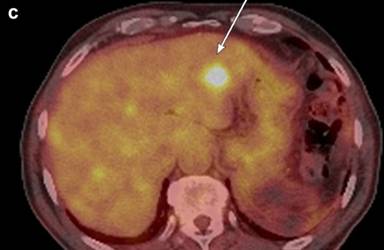

Medical image diagnosis by radiologists is based on their training, experience and individual judgment to visually identify key image features, which aid them in making decisions. Texture analysis is a wide range of methods incorporating image filtering techniques (wavelets, Gabor, grey level co-occurrence matrix, etc.) that can be used to describe variations in image intensity or patterns. Some of these patterns or differences might be imperceptible to the naked eye but texture analysis with statistical pattern recognition techniques can be used to evaluate texture pattern differences in images. A basic routinely used feature, for example, is size. Texture feature analysis of CT images has shown promise in pancreatic cancer [14]. Similarly, work has been done to identify features on FDG-PET images in other tumors, such as esophageal, [15]. Tuli et al. [7] found texture features of the FDG-PET images in a small sample of subjects that correlated with response to SBRT. By using this pilot data and incorporating knowledge gained from work in esophageal cancer, a prospective study would be helpful for further assessment. In addition, some centers routinely use MRI (Figure 1) for staging of pancreatic adenocarcinoma. Feature analysis of MRI images may hold more information [16]. Since gemcitabine interferes with DNA synthesis, MRI techniques like diffusion weighted imaging may be helpful since diffusion weighted imaging is affected by changes in cellular density.

|

Figure 1. A 76-year male with poorly differentiated ductal adenocarcinoma in the tail with perineural invasion and lymphovascular invasion on the resection specimen Total of 4/15 positive lymph nodes were found. Genetic testing was negative for EGFR, KRAS, and BRAF mutations. MRI before surgery shows: a. restricted diffusion on diffusion weighted imaging; b. little to no enhancement two minutes post-contrast injection. c. Follow-up FDG-PET-CT two months later showed multiple metastases in the liver with SUV up to 9.8. |

Aside from texture analysis, several studies reviewed here demonstrated that measures of metabolic or glycolic activity on FDG-PET may hold prognostic value for subjects with early pancreatic adenocarcinoma. Since radiation therapy disrupts DNA and microvessels, imaging techniques like diffusion weighted imaging and dynamic contrast enhanced MRI may correlate with changes in FDG-PET. In a preliminary retrospective study of subjects with hepatocellular carcinoma, Ahn et al. found that SUV on the FDG-PET was inversely related to the dynamic contrast enhanced MRI parameter of perfusion [17]. The PET-MRI systems under development may allow for simultaneous assessment of tumor and identification of prognostic imaging features [18].